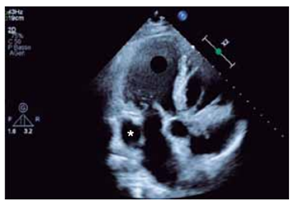

A estrutura indicada pelo asterisco na figura a seguir pode estar associada a

(Arquivo pessoal; imagem utilizada com autorização)